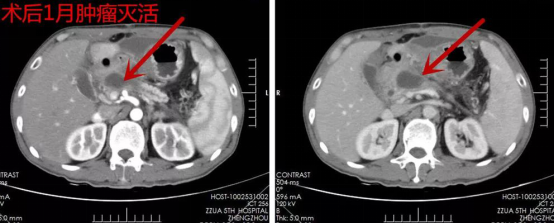

刘某术后来院复诊,1月复查CT肿瘤灭活(图2),3月复查CT肿瘤消除(图3),6月复查CT未见复发及转移(图4),1年复查CT部分胰腺组织萎缩、纤维化,肿瘤未见复发及转移(图5),2年复查CT(图6),病情稳定,未见肿瘤复发及转移。

▲ 图二

▲ 图三